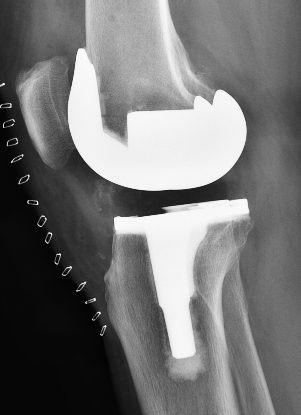

术后次日,患者杨阿姨即在医生指导下进行床旁行走训练,膝关节活动度逐步恢复。杨小海主任医师介绍,全膝关节置换术通过置换磨损的关节表面(类似“换保护套”),可显著改善因关节退变、软骨磨损导致的疼痛,患者术后很快即可恢复日常生活。本次所采用的骨科手术机器人辅助手术,通过三维影像精准规划截骨平面,术中实时调整截骨角度,相较于传统手术,可提升截骨的精准度与假体安放的精确性,缩短手术时间,减小创伤,降低术后并发症风险。杨阿姨术后复查X片显示膝关节假体位置良好,下肢力线合适。